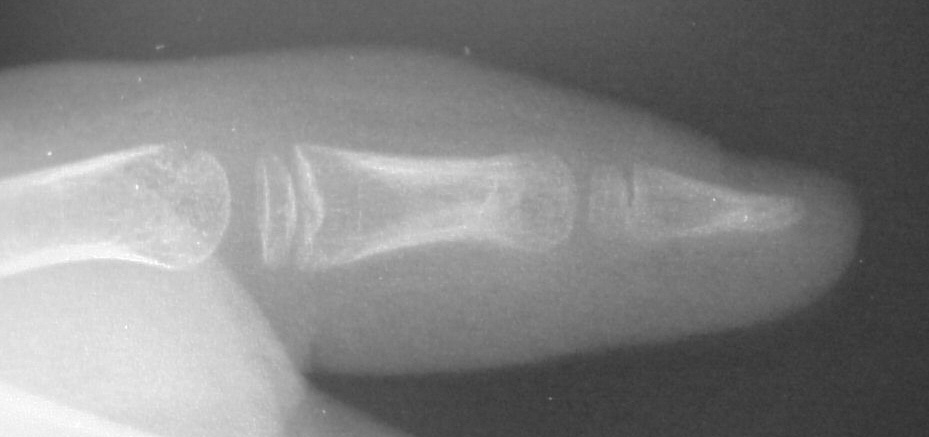

| Case 3. Wassell II duplication of the distal phalanges, reconstructed with proximal phalanx head narrowing, closing wedge osteotomy and radial collateral ligament reconstruction from the deleted segment. |